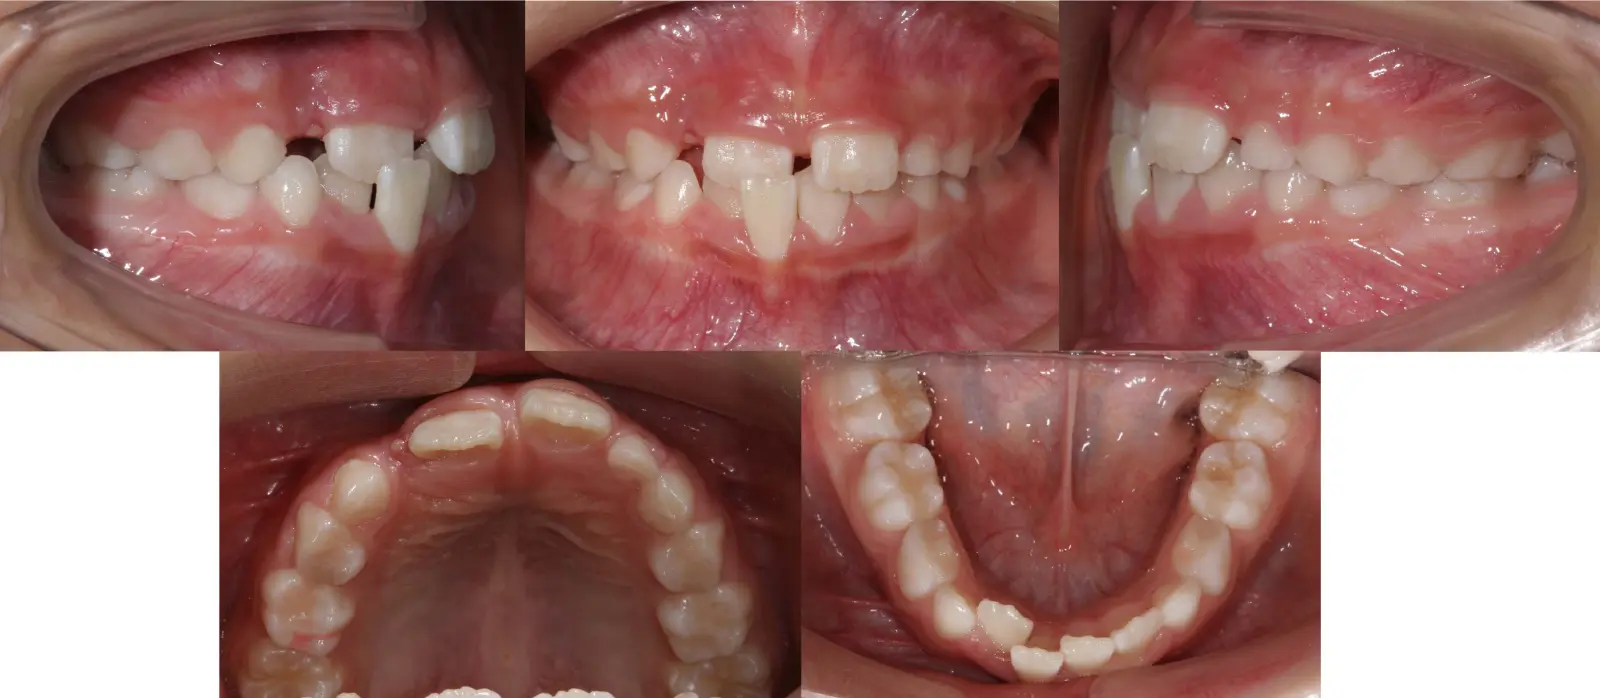

アングルⅡ級 叢生を伴う軽度上顎前突症

第一段階の治療のみで、

永久歯は問題なく萌出し、安定している

- 主訴

前歯のガタガタ

- 年齢

9歳

- 治療期間

10ヶ月

- 治療回数

10回

- 治療に用いた主な装置

拡大床、2by4

- 治療費

400,000円(税別)トータル料金

- 抜歯部位

非抜歯